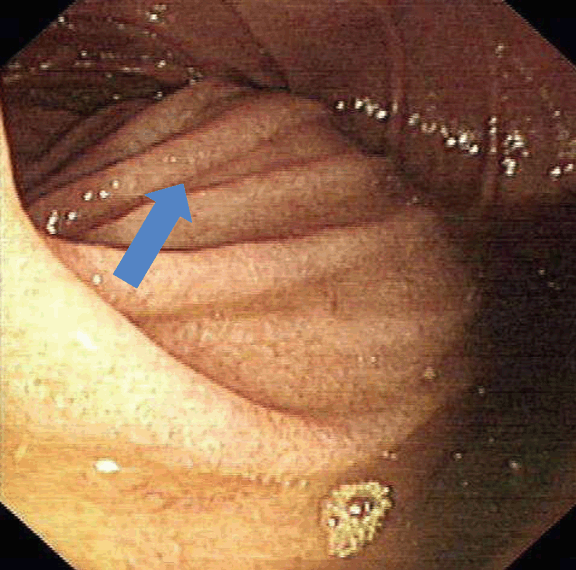

A 64-year-old schizophrenic elderly male was admitted in Singapore government hospital for epigastric pain of 1 day duration associated with a two-day history of vomiting. The character of the vomitus was uncertain. He had lost 30–40 kg of weight over several months. The patient denied postprandial pain and had no previous similar episode. He had no past history of surgery and was not on any psychiatric medication. The patient had paranoid schizophrenia but was never compliant with medications. He lived alone and had persecutory thoughts. He was suspicious of people around him and barred all windows and rooms. He also mentioned cameras watching him and “people” want to harm him. He refused to go out and consumed mainly instant noodles for several years. One month before this admission, he was admitted for hypoglycemia secondary to poor oral intake and incidentally had low calcium and vitamin D deficiency. His vital signs were stable on admission. He appeared comfortable but was severely cachectic with a body mass index of 10.9 kg/m2 (weight 34.4 kg, height 178 cm). The abdomen was scaphoid, distended and tender over epigastric area with no sign of peritoneal irritation and succussion splash was positive. Per rectal examination was unremarkable. Initial laboratory studies were largely unremarkable besides the elevated total white, low creatinine and urea. Supine and erect plain abdominal radiograph showed a grossly distended stomach and collapsed bowel distally. (Figure 1) In view of the distended abdomen, positive succession splash and dilated stomach on abdominal radiograph, our initial impression was gastric outlet obstruction. Patient was kept nil by mouth and nasogastric tube was inserted to maintain gastric and duodenal decompression. Nasogastric tube immediately aspirated 2.2 liters of bilious fluid. Upper gastrointestinal series showed distended stomach and duodenum to the level of mid third part, where an abrupt cut-off occurred. (Figure 2) To determine the aetiology, contrast-enhanced computed tomography (CT) scan of the abdomen was arranged and the third portion of the duodenum was clearly ‘pinched’ by the abdominal aorta and the superior mesenteric artery. The aorta-SMA angle was 4 degrees and the aortomesenteric distance measured 5.6 mm. (Figure 3) (Figure 4) In addition, CT scan also revealed obvious reduction of the intra-abdominal fat. There was no free intraperitoneal air. Based on the history, examination and imaging findings, we diagnosed SMA syndrome. Endoscopic guided insertion of nasojejunal tube was performed for enteral feeding as patient was unable to tolerate any oral intake due to duodenal obstruction. (Figure 5) However, the patient was not cooperative with nasojejunal tube feeding. Subsequently, he developed hypoglycemia, hypokalemia and hypotension that was refractory to resuscitation. Consciousness deteriorated and the patient passed away. | ||||||

Superior mesenteric artery syndrome was first described by Austrian Professor Carl Freiherr Von Rokitansky in 1861. [3] Later Wilkie published the first comprehensive case series of 75 patients with what he initially called “duodenal ileus”, 64 of who underwent duodenojejunostomy. Wilkie’s detailed anatomical, clinical and pathophysiological description of extrinsic compression of third portion of duodenum by the superior mesenteric artery has become a common eponym for SMA syndrome. [4] Subsequently, a variety of other names have been used such as chronic cast syndrome and arteriomesenteric duodenal compression syndrome. [5] [6] Superior mesenteric artery originates acutely from the abdominal aorta behind the neck of the pancreas at the level of first lumbar vertebra and travels caudally into the root of mesentery. The transverse portion of the duodenum crosses anterior to the third lumbar vertebra and was separated from the superior mesenteric artery by the retroperitoneal fatty tissue. The normal angle between abdominal aorta and the superior mesenteric artery is 25–60° and the aortomesenteric distance is around 10–28 mm. [7] [8] Such relationship correlates with body mass index. [2] Pathophysiological loss of retroperitoneal and paraduodenal fats can result in aortomesenteric distance less than 8 mm and aorto-SMA angle of 22° or less, resulting in duodenal ‘clamping’. Such pathophysiology can be seen in chronic wasting disease, catabolic state, anorexia and malabsorption. Surgical interventions can occasionally alter the anatomical relationship, jeopardizing the aortomesenteric angle and resulting in SMA syndrome (e.g., scoliosis surgery, aortic aneurysm repair, bariatric surgery). [1] [5] The SMA syndrome can present acutely or chronically with signs and symptoms of proximal gastrointestinal tract obstruction (i.e., nausea, vomiting, weight loss, sense of repletion and postprandial abdominal distension). Such presentations, however, are nonspecific to SMA syndrome and diagnosis is frequently delayed. Henceforth, a high index of suspicion is required and a comprehensive investigation is recommended to rule other conditions that are common and has different treatment implication including pancreatitis and peptic ulcer disease. [9] Upper gastrointestinal series, contrast-enhanced computed tomography (CT) scan, magnetic resonance angiography (MRA), ultrasound (US) and endoscopy are modalities that can be utilized to establish diagnosis. Our patient had upper gastrointestinal series that revealed a classical dilated proximal duodenum with abrupt contrast cut-off at the transverse portion of duodenum. Computed tomography scan of abdomen with contrast can clearly demonstrate the obstruction site, determine the aetiology of the obstruction and allows evaluation of aortomesenteric angle and aortomesenteric distance, both of which are sensitive measures of diagnosis. An aortosuperior mesenteric artery angle of less than 25° and aortomesenteric distance less than 8 mm are highly suggestive of SMA syndrome. [9] In our patients, both parameters were reduced with angle and distance of 4° and 5.6 mm, respectively. Upper endoscopy can be used to rule out stenosing lesions in the duodenum. With the advent of noninvasive radiological studies, conventional arteriography is rarely needed in the workup of SMA syndrome except in cases where diagnosis is not clear. The treatment of SMA syndrome can be either conservative or surgical. Patients with SMA syndrome initially require nasogastric tube insertion for gastrointestinal decompression, fluid resuscitation, correction of electrolyte abnormalities and early nutritional support. Nutritional support aims to promote body weight gain and restore the retroperitoneal fat tissue with subsequent increase in aortomesenteric angle and reduction in duodenal obstruction. Nasojejunal tube that is placed distal to the obstruction allows enteral administration of nutrition. Parenteral nutrition may be an alternative but it is not without its associated complications. Notably, patient should be monitored for refeeding syndrome during nutritional rehabilitation as these patients are malnourished and are susceptible to electrolyte and fluid shifts. Duration to achieve symptomatic improvement is variable in conservative nutritional treatment and has been documented to range from 2–169 days. [1] Patients with shorter history of SMA syndrome have higher success rate with conservative management. On the other hand, those with more chronic history have a prolonged hospital stay with low success rates of conservative treatment alone and surgery after a period of refeeding and weight gain is indicated. [8] Several surgical options have been proposed to resolve or bypass the duodenal compression including Strong’s procedure (caudal mobilization of duodenojejunal flexure by division of ligament of Treitz), gastrojejunostomy and duodenojejunostomy. The advantage of Strong’s procedure includes maintaining bowel integrity, easier and quicker to perform and less invasive and is a safer procedure. [9] However, Strong’s procedure has high failure rate of 25% and presumably due to difficulty in mobilizing the duodenum with interference from intra-abdominal adhesions and the short vessels of the inferior pancreaticoduodenal artery. Gastrojejunostomy can decompress the stomach adequately but it does not resolve the duodenal obstruction and the patient can have persistent symptoms. Furthermore, such bypass operation can cause blind loop syndrome, gastric bile reflux and peptic ulceration that necessitate second operation (i.e., duodenojejunostomy). Duodenojejunostomy is the surgical treatment of choice and can be performed with or without division of fourth portion of the duodenum. It has a reported a success rate of 90%. [10] | ||||||